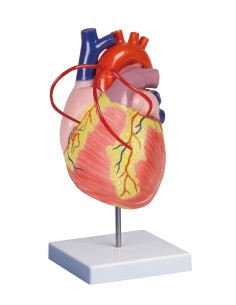

Du crâne en 22 parties à verrouillage magnétique aux modèles de colonne vertébrale, des modèles d'articulation aux modèles de cœur, chaque pièce de notre collection est conçue pour une immersion totale dans l'étude de l'anatomie humaine. Nos modèles, réalisés à partir de scans d'os réels, garantissent une expérience tactile authentique et une fidélité de poids presque identique aux originaux.